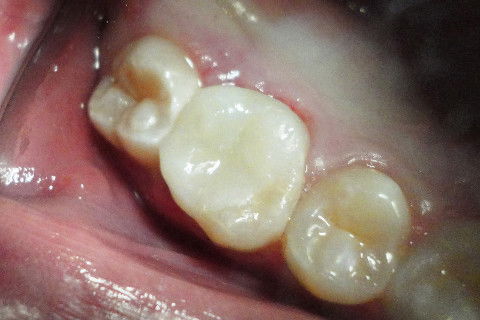

Aspecto Clínico Inicial